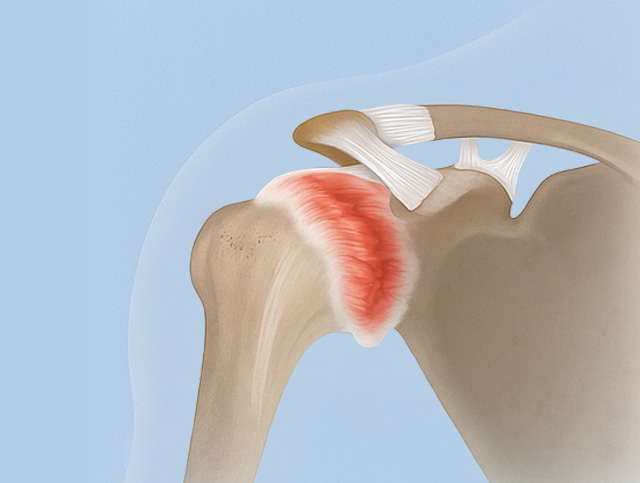

유착성 관절낭염

(오십견)

특별한 외상 없이 어깨관절을 움직이기 어렵고 심한 통증 발생

노화, 어깨 부상 등으로 움직임 제약, 관절 주위 연조직의

퇴행성 변화로 발생